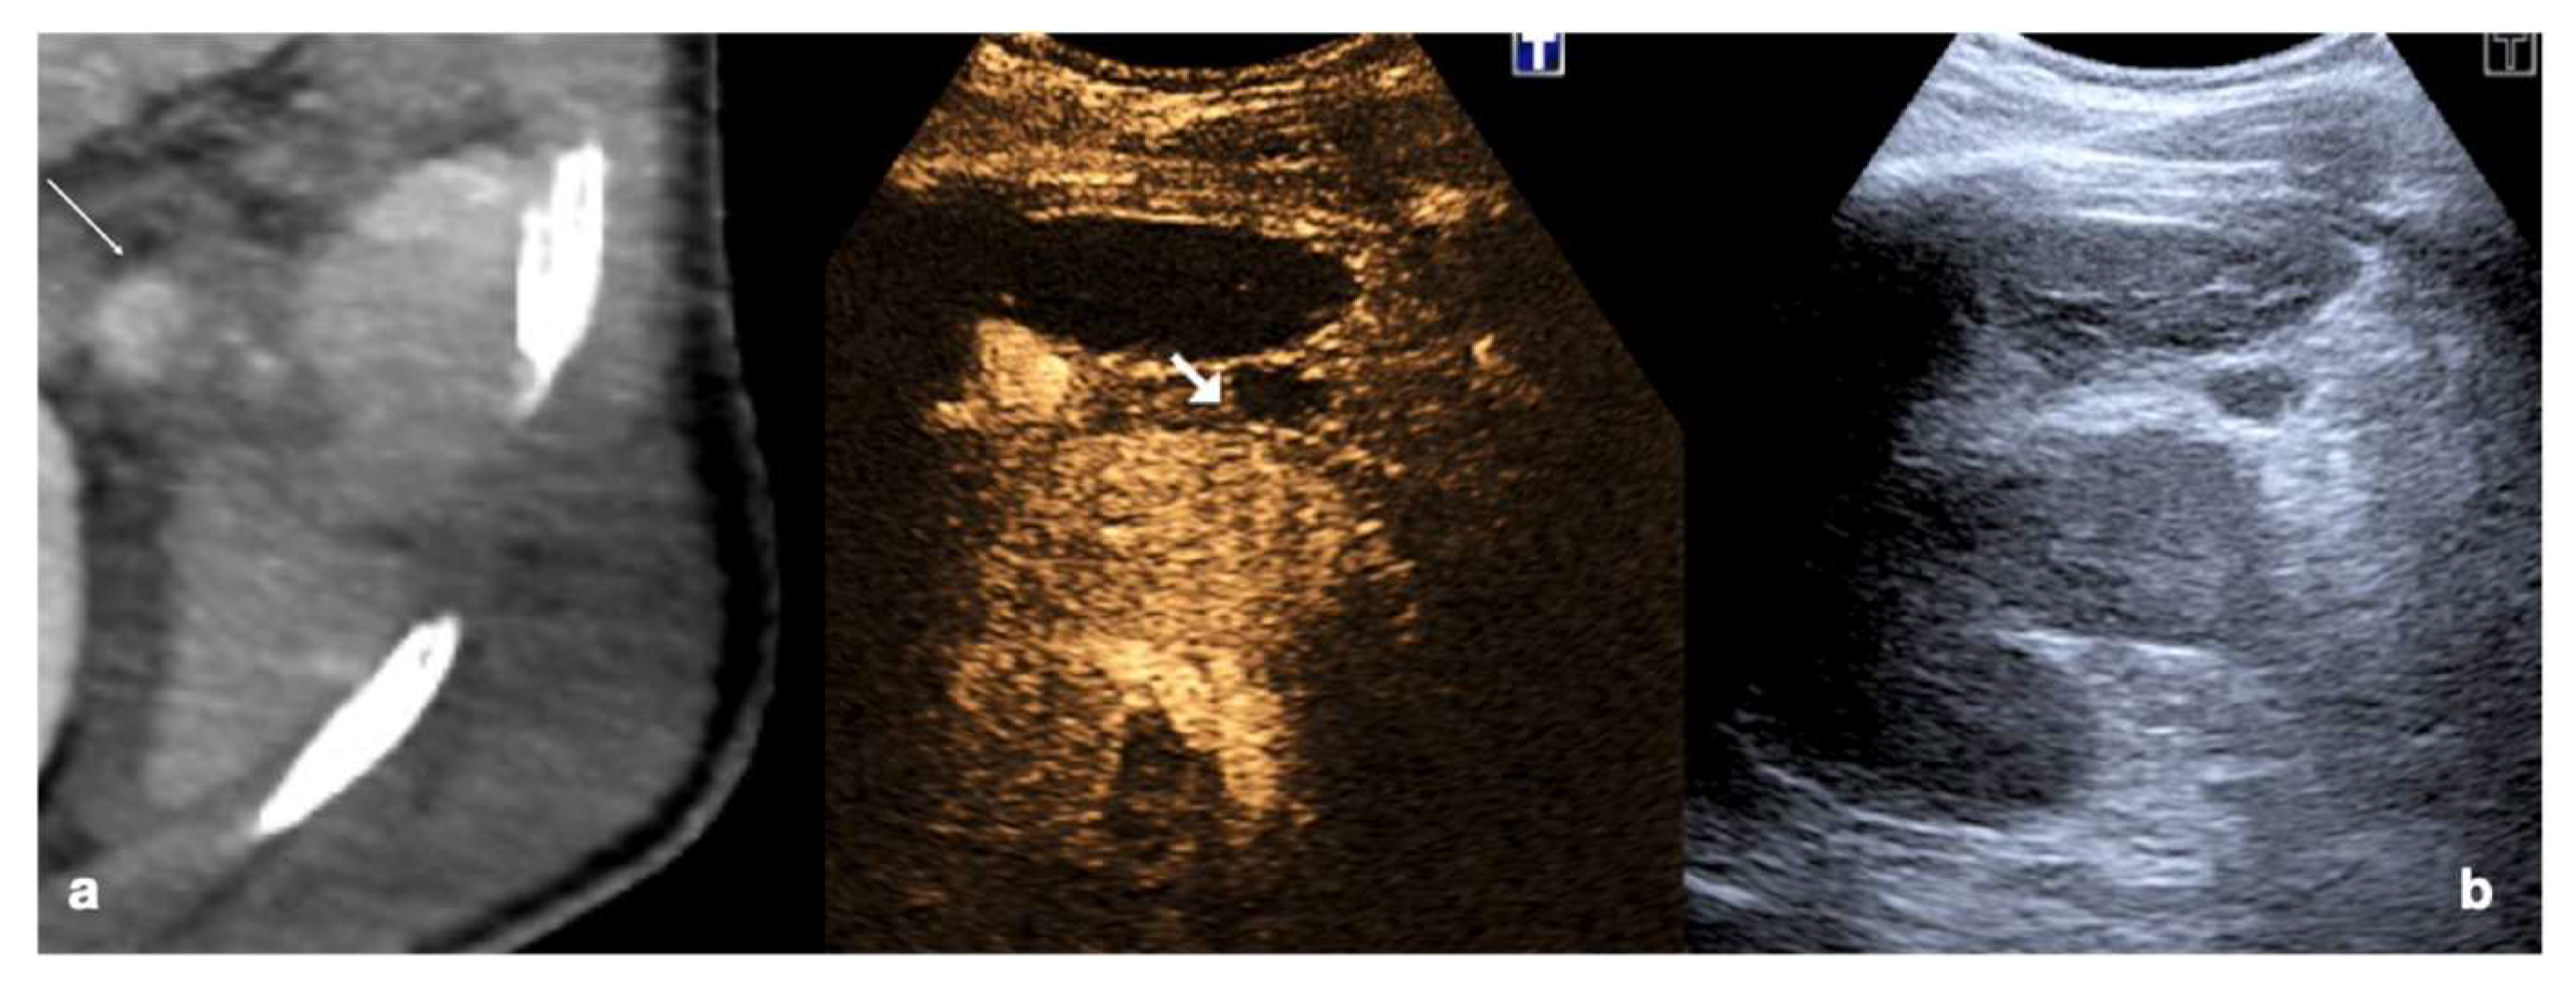

Follow-up CEUS of a 52−year-old blunt trauma patient with high-grade right kidney injury and extensive ischemia complication. Venous (a) phase CEUS examination shows multiple kidney lacerations with extensive ischemia complication and a small amount of perfused renal (caliper). At the same venous phase (b), CEUS active venous hemorrhage is well appreciated (arrow) confirmed at contrast-enhanced venous phase CT scan (c, arrow) and subsequent angiography (d).